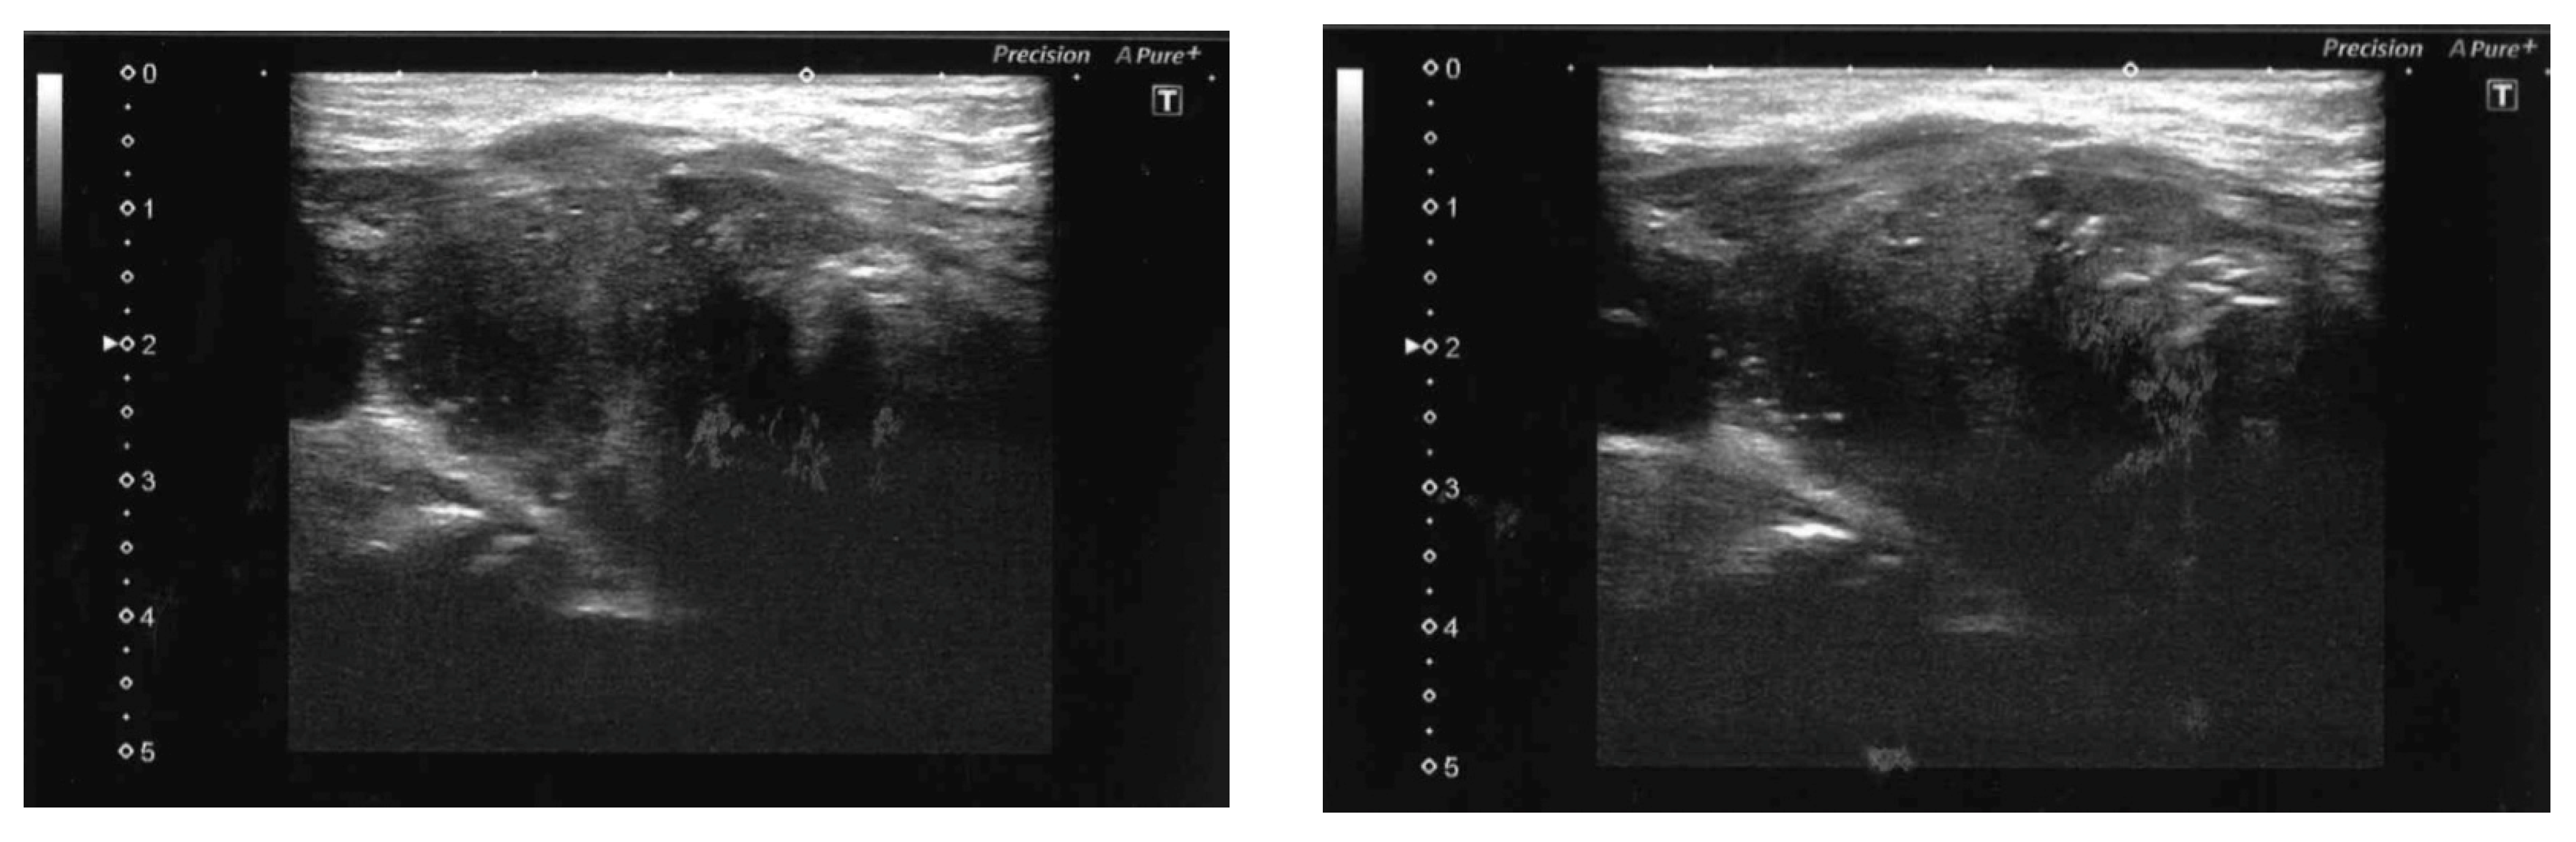

- Zhang, Y.; Xue, S.; Wang, Z.; Jin, W.; Chen, Z.; Chen, G.; Zhang, Q. Thyroid metastasis from breast cancer presenting with enlarged lateral cervical lymph nodes: A case report. World J. Clin. Cases 2020, 8, 838–847. [Google Scholar] [CrossRef]

- Lee, D.H.; Yoon, R.G.; An, J.K.; Woo, J.J. Ultrasonographic Features and the Diagnostic Role of Core Needle Biopsy at Metastatic Breast Cancer in the Thyroid gland: A Case Report. Taehan Yongsang Uihakhoe Chi. 2020, 81, 719–725. [Google Scholar] [CrossRef]

- Jung, H.K.; Kim, B.; Ryu, J.H. Intrathyroid metastasis of breast cancer: Sonographic findings. J. Clin. Ultrasound. 2021, 49, 488–491. [Google Scholar] [CrossRef] [PubMed]

- Hoshi, M.; Jikuzono, T.; Suzuki, S.; Ishibashi, O.; Kawamoto, Y.; Kure, S.; Kawamoto, M.; Ohashi, R.; Sugitani, I. Use of ultrasonographic shear wave measurements to diagnose thyroid metastasis from breast carcinoma. J. Nippon Med. Sch 2022. Epub ahead of print. [Google Scholar] [CrossRef] [PubMed]

- Zhang, K.; Yu, Y.; Zang, Y.; Xu, H.; Lv, B.; Wang, Q. Case report: Unique ultrasound feature of thyroid metastases in occult breast cancer. Front. Oncol. 2022, 12, 970286. [Google Scholar] [CrossRef]

- Saito, Y.; Sugitani, I.; Toda, K.; Yamada, K.; Fujimoto, Y. Metastatic thyroid tumors: Ultrasonographic features, prognostic factors and outcomes in 29 cases. Surg. Today 2013, 44, 55–61. [Google Scholar] [CrossRef] [PubMed]

- Debnam, J.M.; Kwon, M.; Fornage, B.D.; Krishnamurthy, S.; Clayman, G.L.; Monroe, B.S.E. Sonographic Evaluation of Intrathyroid Metastases. J. Ultrasound Med. 2017, 36, 69–76. [Google Scholar] [CrossRef] [PubMed]